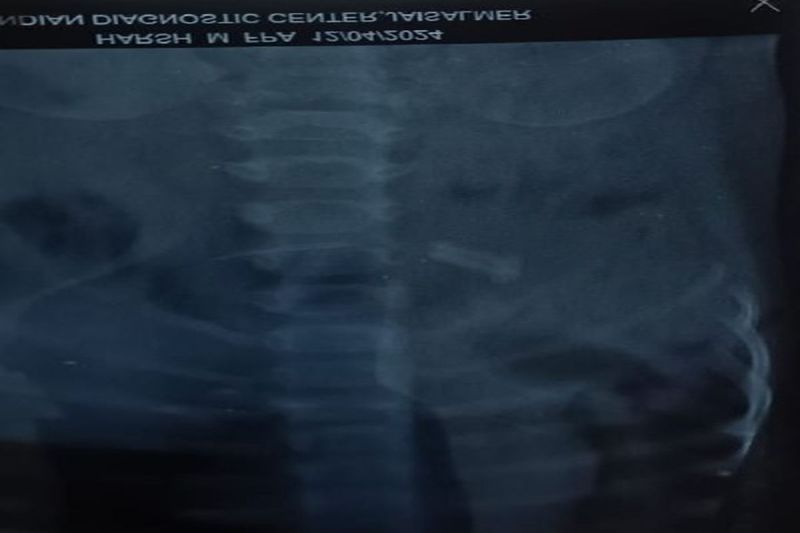

सवा वर्ष के एक बालक ने खेलते हुए 2 इंच के नुकीले लोहे के स्क्रू को निगल लिया। कुछ ही देर में उसकी तबीयत बिगडऩे लगी। माता-पिता उसे जिला मुख्यालय स्थित राजकीय जवाहिर अस्पताल लेकर गए, जहां चिकित्सकों की सूझबूझ से बिना ऑपरेशन के स्कू्र को उसके शरीर से बाहर निकाला गया। जानकारी के अनुसार जिले के रासला निवासी अमृत लाल देवपाल के सवा वर्ष के बच्चे हर्ष ने शुक्रवार दोपहर करीब 3 बजे खेलते हुए लोहे का बड़ा और नुकीला स्कू्र मुंह में निगल लिया। तबीयत बिगडऩे पर वह रोने लगा। हर्ष के पिता अमृतलाल और उसकी माता उसे राजकीय जवाहिर अस्पताल लेकर आए, जहां शिशु रोग विशेषज्ञ भवानी परिहार ने बच्चे की जांच की। एक्सरे में पेट में नुकीला स्कू्र होने की जानकारी सामने आई। इस पर चिकित्सक भवानी शंकर परिहार ने सर्जन डॉ. सत्ताराम से परामर्श लिया और दोनों चिकित्सकों ने पीडि़त बच्चे का ऑपरेशन न कर उसको 24 घंटे अपने ऑब्र्जवेशन में रखने का निर्णय लिया। इस दौरान डॉक्टर्स ने बच्चे को दवाई व खाने में केले और हलुआ खिलाने की सलाह दी। शनिवार सुबह 10 बजे नुकीला स्कू्र मल के रास्ते के साथ बच्चे के शरीर से बाहर निकल गया। चिकित्सकों के अनुसार बच्चा स्वस्थ हैं तथा उसे हॉस्पिटल से डिस्चार्ज कर दिया गया है।